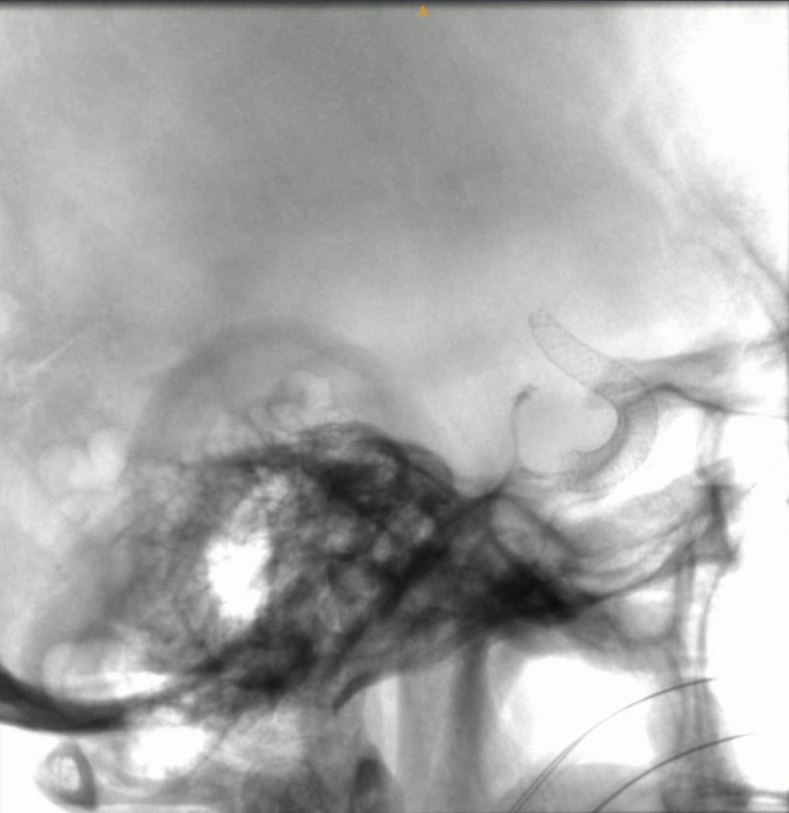

术中Dyna CT提示支架释放良好

术中影像融合提示支架贴壁良好